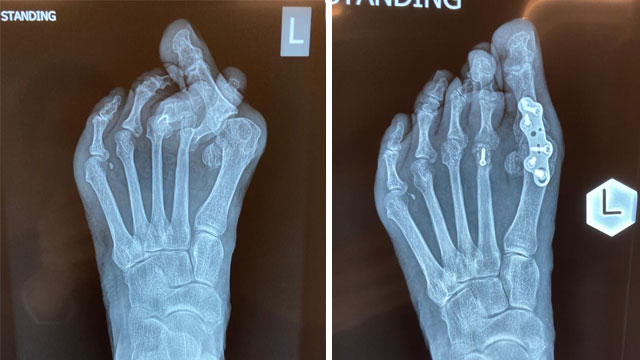

拇趾外翻是形容大拇指向外側移位,令大拇指第一關節腫大突出及發炎。成因可以是先天骨骼問題,或因後天的影響,例如長期穿著窄身或高跟鞋。

<手術方法>

* 中度病情

使用截骨方法來修正突出的骨頭,將拇指關節角度修復至正常狀態

嚴重病情

* 將趾骨關節修復至正常狀態後,再以螺絲和鋼板融合,減低復發機會